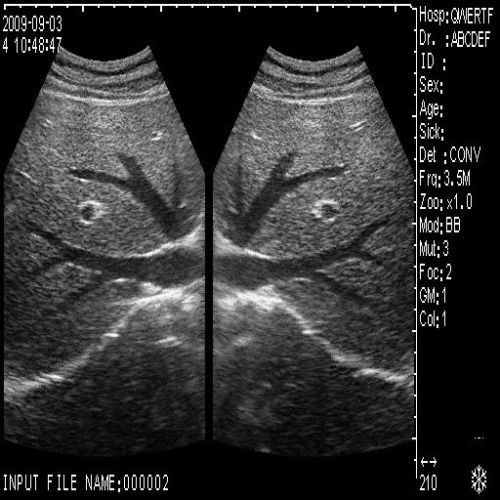

Comprehensive Ultrasound Scanner for Pregnancy

image: +3D High clear

Probe Function: 3.5MHZ convex, abdominal organs

Probe 2: 7.5MHZ Transvaginal probe:gynecologic examination

The Ultrasound Scanner utilizes cutting-edge imaging technology, allowing for detailed and accurate evaluations during pregnancy. With capabilities for both convex and transvaginal scanning, this device provides versatile options for healthcare professionals. It is essential for monitoring fetal development and ensuring the health of both the mother and the unborn child. Doctors can easily select the appropriate probe, enabling them to capture high-resolution images that are critical for diagnosis and treatment.